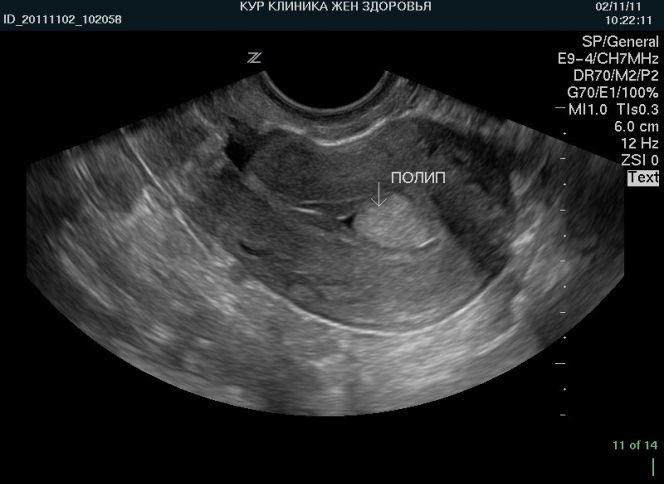

Полипы эндометрия

На ультразвуковом исследовании (УЗИ) могут быть выявлены полипы, которые выглядят более светлыми. Эти образования формируются из железистой или соединительной ткани с низкой плотностью. Их появление связано с действием гормона эстрогена, и в большинстве случаев они являются доброкачественными. Полипы имеют четкие контуры и характерную форму, что позволяет легко их диагностировать. Вероятность ошибки при их выявлении крайне мала.

Рекомендуется удалять такие новообразования, так как они могут вызывать серьезные симптомы. Кроме того, существует риск их трансформации в злокачественные образования.

Гиперэхогенная зона, прикреплённая к стенке матки, что указывает на место прикрепления полипа. Место прикрепления может быть видно как яркая точка или линия, исходящая от стенки эндометрия. Отсутствие акустической тени за полипом, что отличает его от других структур, таких как миомы или кальцификаты.